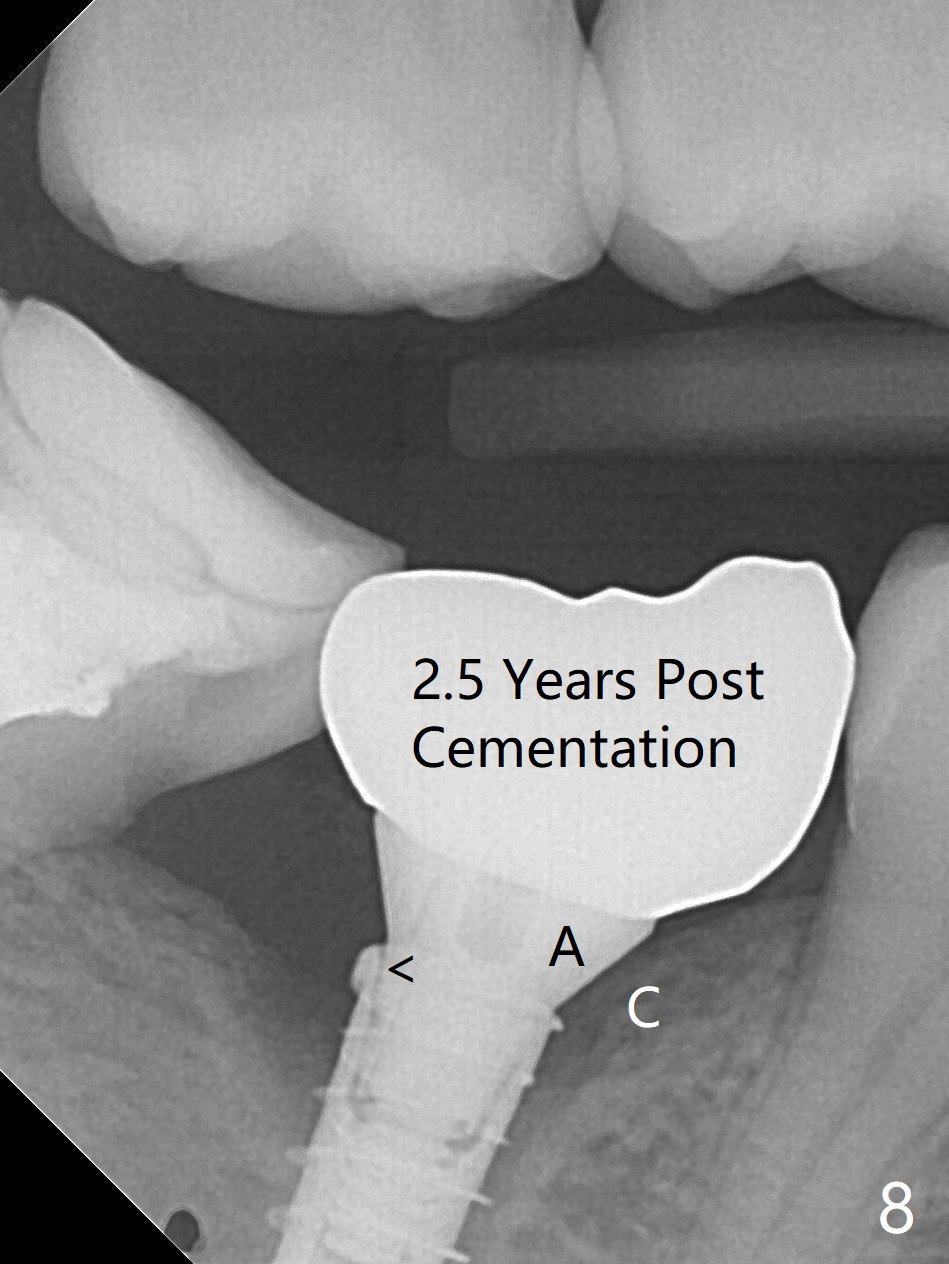

There is no apparent bone loss 4 months postop (Fig.7), related to the advantage of the narrow implant (less traumatic). The crown/abutment is loose 2.5 years post cementation due to incomplete abutment seating (Fig.8 < (no clearance between the abutment (A) and the mesial crest (C))). A 6x3 mm healing abutment is placed. When the patient returns, try in the smallest abutment with 2 mm cuff in the Planning Kit and place probably a 4x4(3) mm pair abutment from 5x4(2) mm existing one. Torque and take PA with sensor 1 to confirm seating before impression. Or use 5.5 mm profile drill before reseating the crown/abutment.